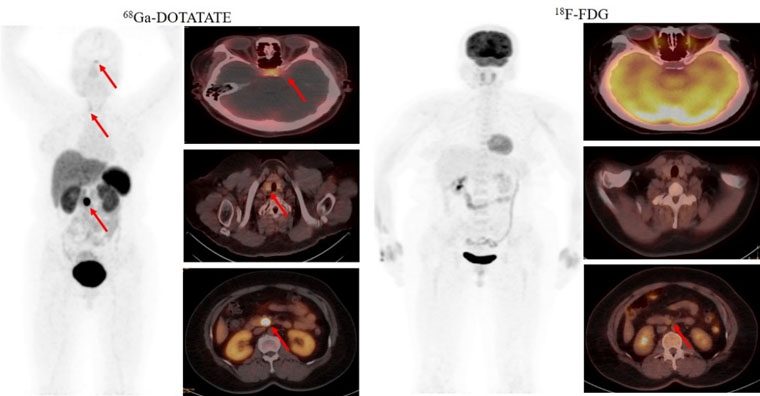

首个病例患者为一名49岁的女性,间断低血糖超过1年,甲状旁腺激素检查异常升高。脑MRI提示为脑垂体微腺瘤,上腹部MRI检查未发现明显异常。但临床怀疑胰腺存在病变,经新探针68Ga-DOTATATE PET/CT检查,发现了胰腺病灶,综合诊断多发性内分泌瘤病I型(MEN1型)。经胰腺穿刺病理证实为神经内分泌肿瘤G2。68Ga-DOTATATE及18F-FDG PET/CT双核素的检查结果为患者临床精准诊疗提供了胰腺病灶的影像学证据。